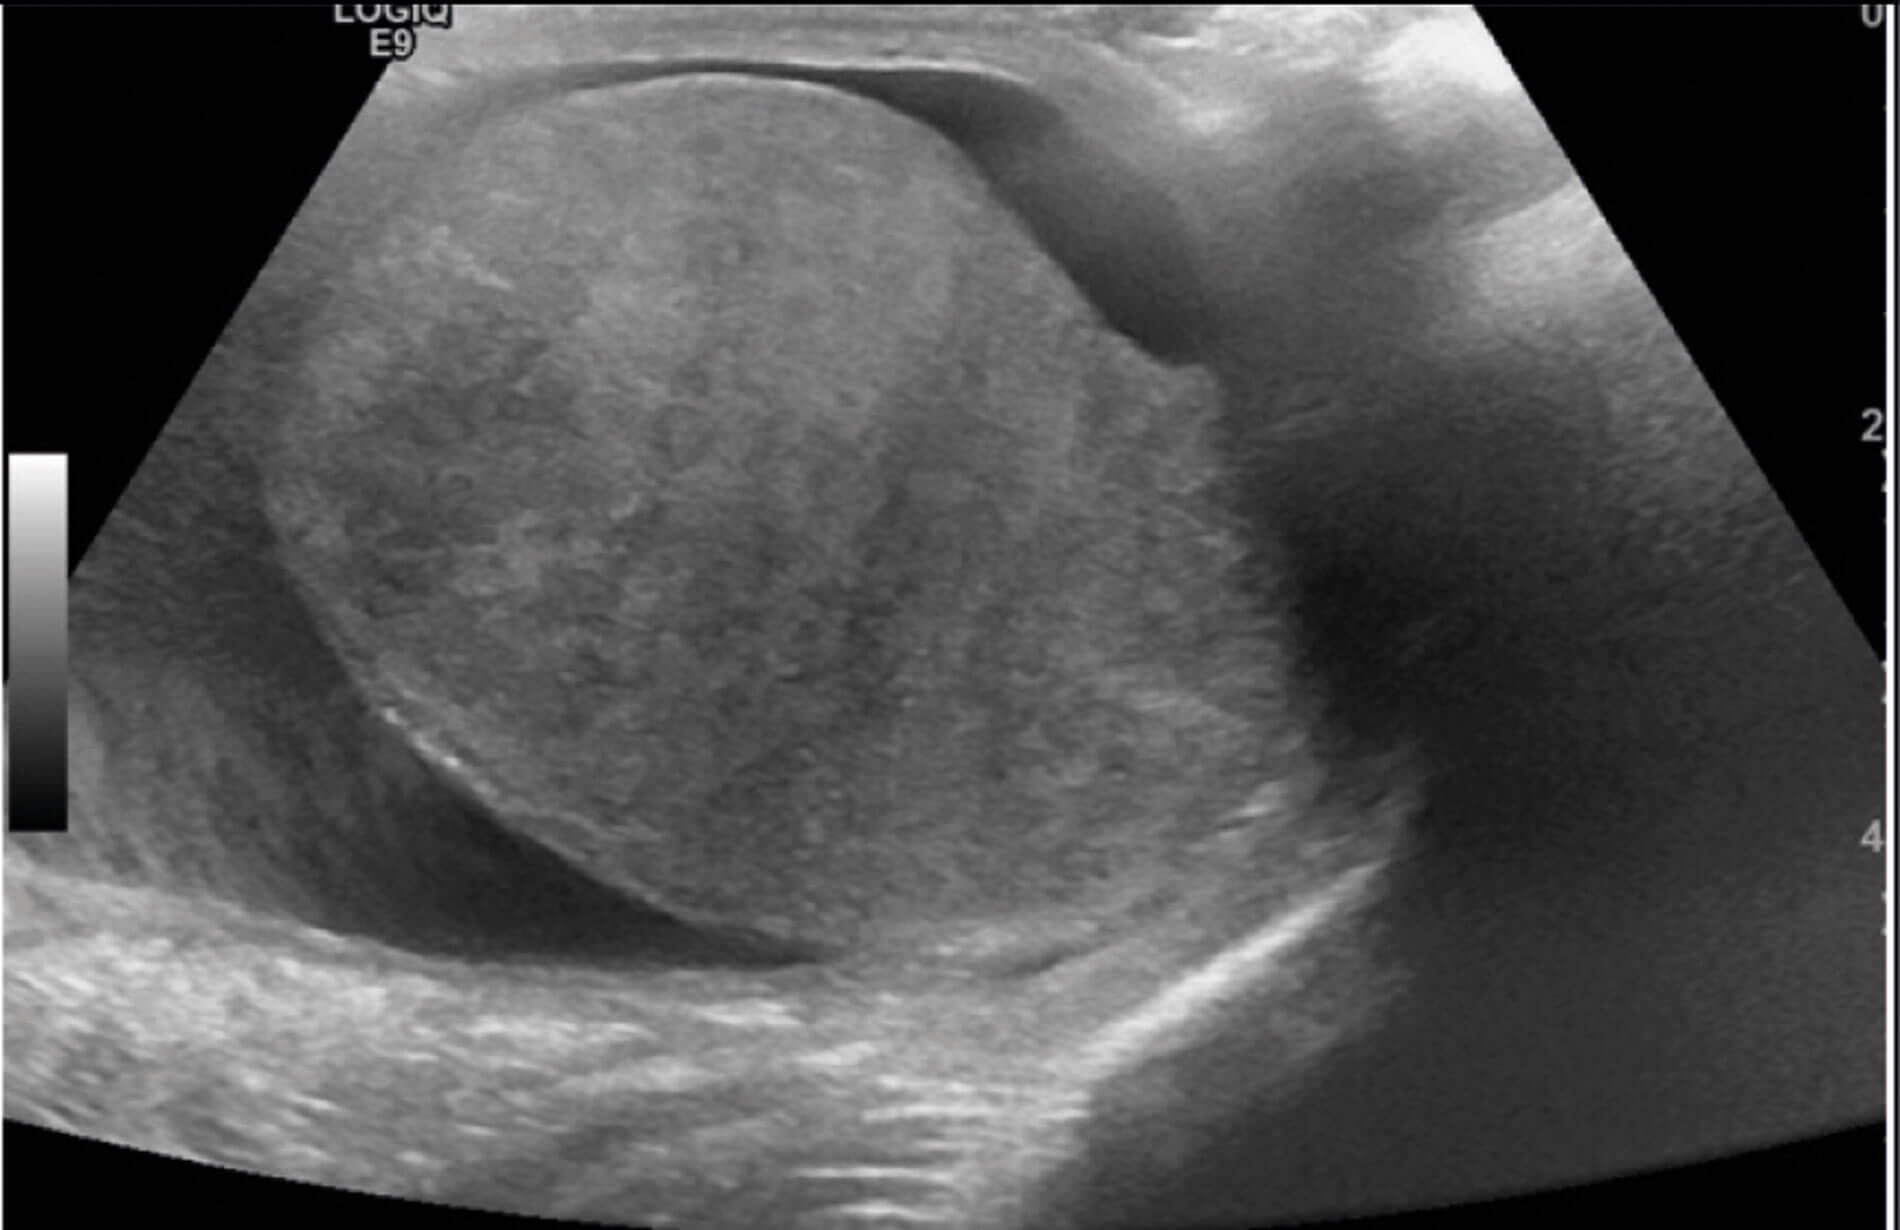

He presented again after completion of the antibiotics with ongoing symptoms and pain. He had another ultrasound performed four weeks later which concluded a resolving epididymo-orchitis. However, the testis was getting larger in size with some heterogeneity. The ultrasound images were reported as inconclusive. He was prescribed another course of antibiotics and re-assessed in another two weeks with a repeat ultrasound that showed enlarging testis.

He sought a second opinion from our hospital. A further ultrasound was performed and images were compared. This confirmed a solitary right testis infiltrated by a poorly defined mass of mixed echogenicity. The mass also showed increased vascularity. There was a surrounding hydrocele measuring 100ml with an empty left hemiscrotum.

Figure 1: US in August 2021.

Figure 2: US in early October 2021.

Figure 3: US in late October 2021.

Figure 4: US in November 2021.